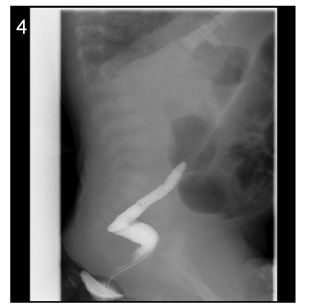

Fig. 4

Image of barium enema at the age of 43days (Case No. 4).

The contrast cannot advance further.

Fig. 4 Image of barium enema at the age of 43days (Case No. 4). The contrast cannot advance further.